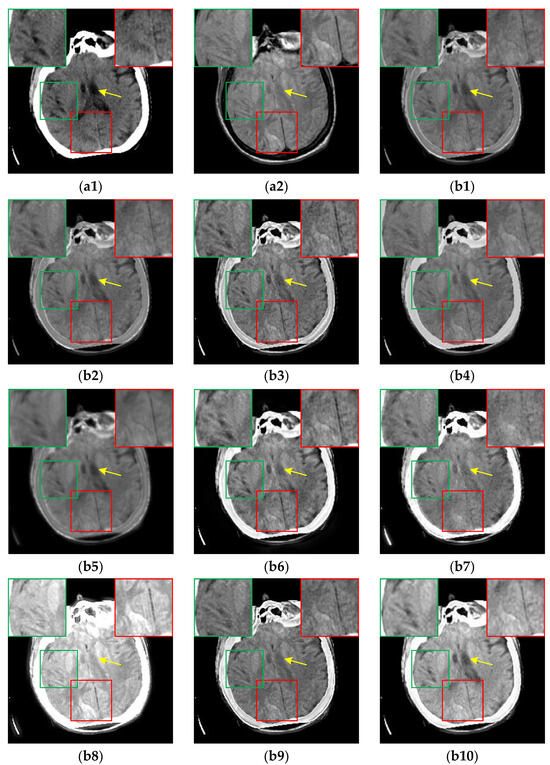

Figure 9. The results of all algorithms on the CT-MR image pairs from RIRE dataset. (a1) Source CT image; (a2) Source MR image; (b1) U2Fusion; (b2) DenseFuse; (b3) IFCNN; (b4) NestFuse; (b5) RFN-Nest; (b6) PAPCNN; (b7) ReLP; (b8) TIF; (b9) CDDFuse; (b10) CIRF.

For the CT-MR image pairs from the RIRE dataset, the results are shown in Figure 9. It is evident that CIRF produces clearer image details, higher image contrast, and less loss of original information. However, U2Fusion, DenseFuse and RFN-Nest fail to effectively fuse the bright cranium from the CT image as depicted by the green arrows. As shown by the yellow arrows, IFCNN, NestFuse, PAPCNN, ReLP and CDDFuse fail to retain the low-intensity areas in the MR image, and TIF produces blocky artifacts. Besides, NestFuse and CDDFuse result in a serious loss of structural information as pointed out by the red arrows.